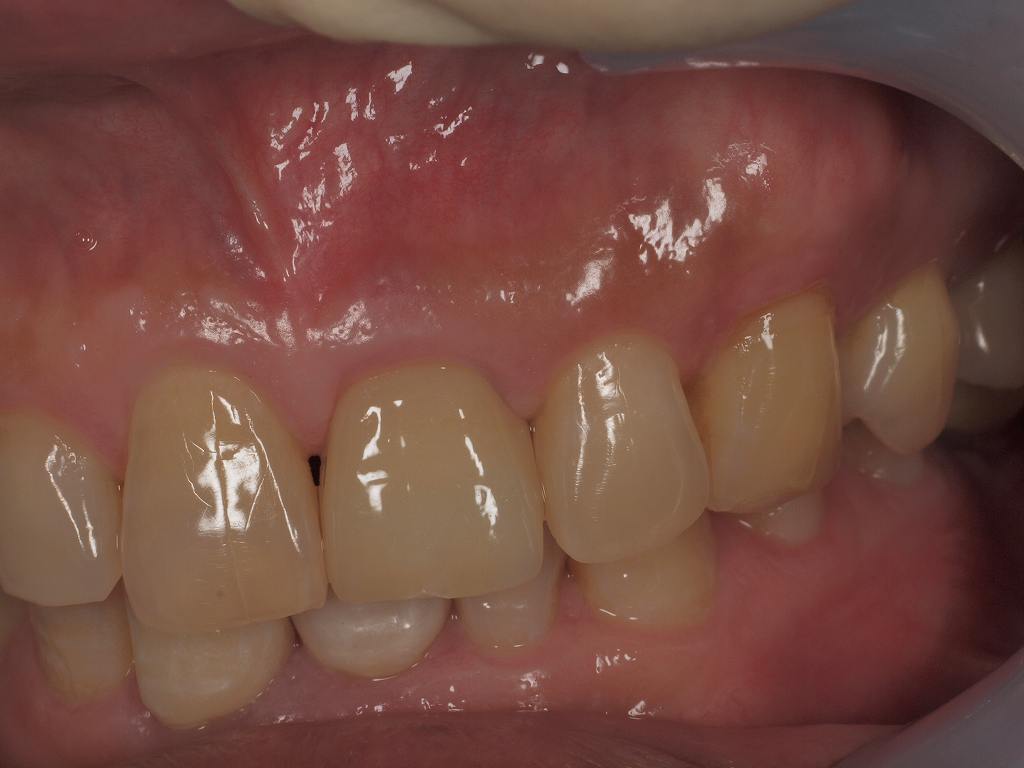

最終補綴時になります

ジルコニアクラウンいて仕上げています

天然歯よりも歯頚線ラインが抜歯しているにも関わらず下がっていないのが良いところかと

歯冠幅径をもう少し隅角を張り出させたりで同じにできたらよかったと思います